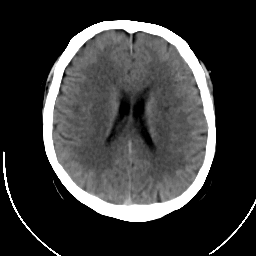

CT Study #1 -- Slice #14

[Home][Help][Clinical][Tour 1] Slice 14